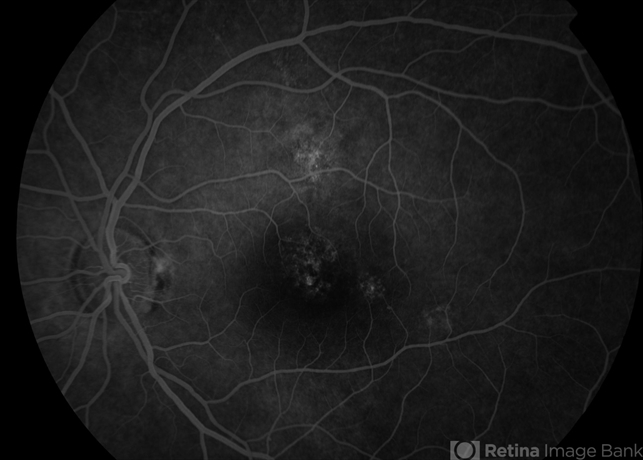

- central serous retinopathy (CSR)

Topcon TRC 50 DX (IA) - Description

- Male patient, 42-years-old. On examination his vision in the right eye is 6/6 & left eye is 6/60. It seems to be a case of central serous retinopathy (CSR) in both eyes.